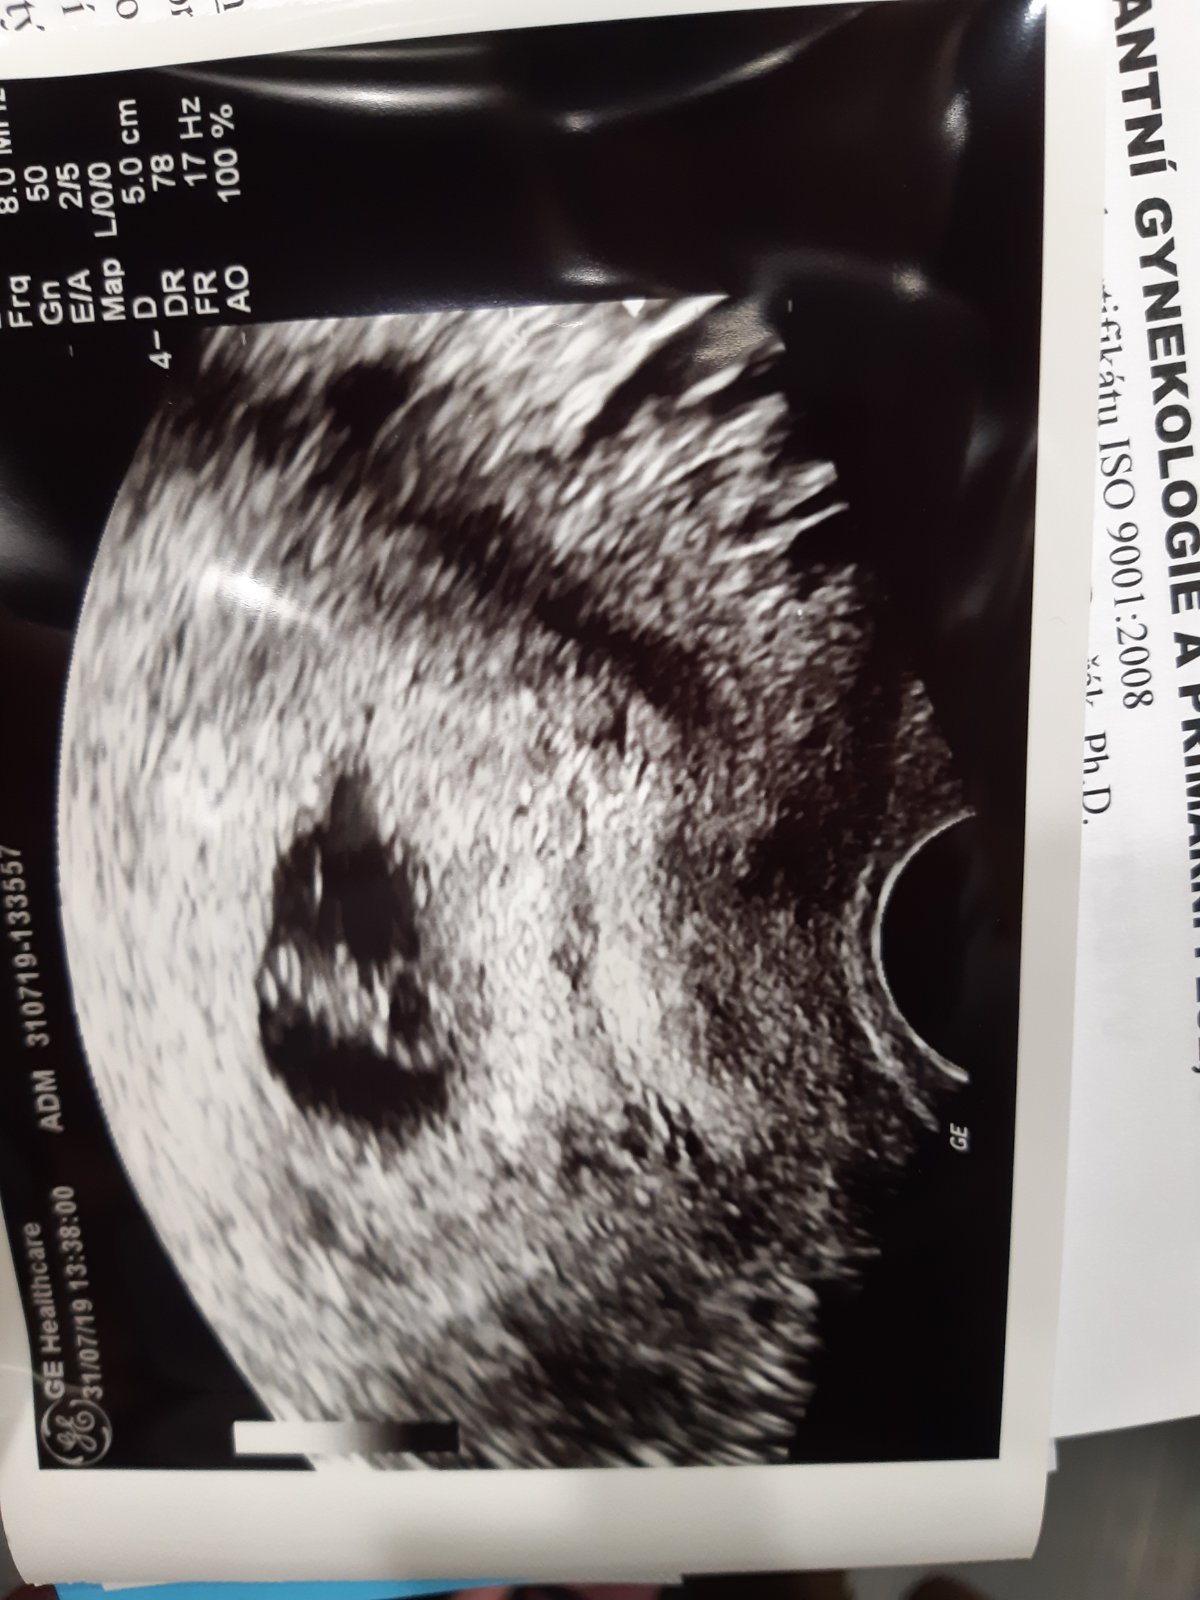

Já řekla hned při duchovi... dva dny před MS... přece kdyby to nevyšlo, budeš ty taky zklamaná, tak proč v tom nebýt spolu... nevím, tohle mi přijde zvláštní že to někdo dokáže před partnerem tajit třeba do první kontroly nebo ještě déle... já jdu k dr teprve dnes, 8tt a neumím si představit, že bych mu to za celou dobu neřekla... i dceru jsem.mu řekla hned ten den, co jsem to zjistila...